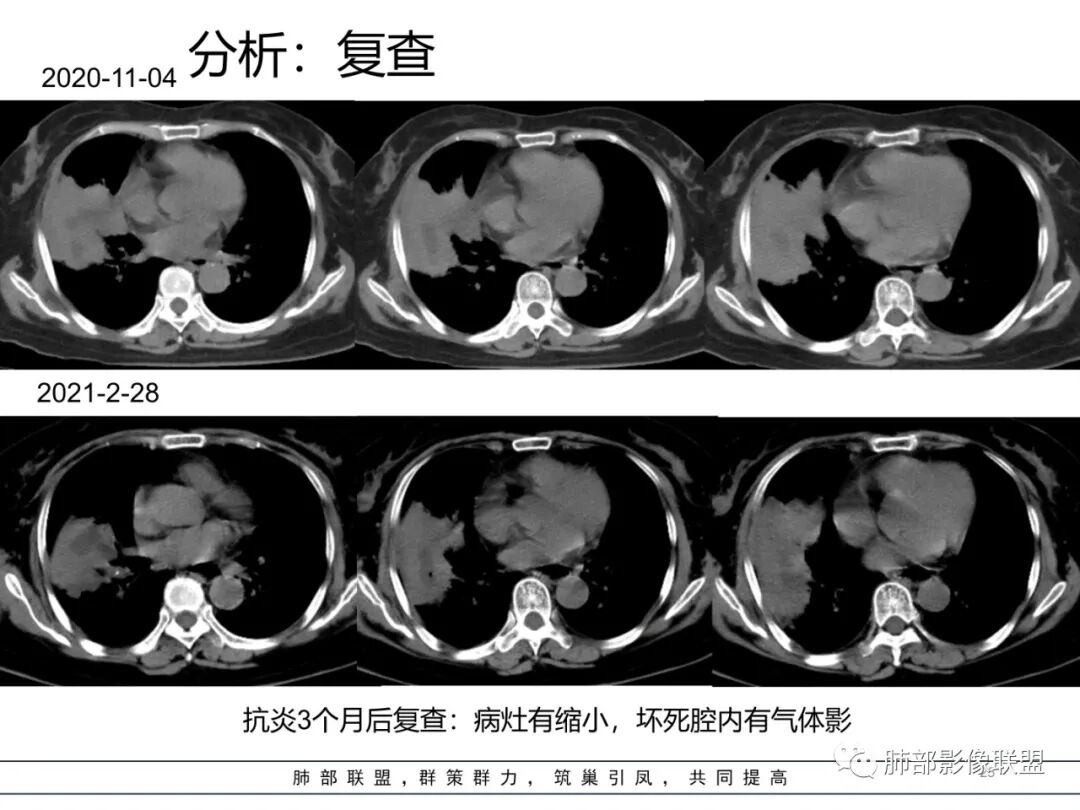

右肺中叶大片实变,内见大片的坏死,中叶外侧段支气管阻塞,相邻胸膜增厚,间隔约四个月后复查,发现低密度坏死内可见气泡影,老年人,反复迁延不愈的病变要考虑恶性,首先考虑腺癌伴感染。鉴别慢性脓肿。

老年女性,慢性病史,炎性指标稍高,肿标正常,右中下肺大片实变,跨叶生长,边界清,收缩力差,膨隆生长为主,支气管杵状截断,均匀强化,其内坏死边界清,可见悬浮气泡,整体观察,病灶膨隆生长为主,邻近肺野无播散灶,形态单一,尽管慢性病史,影像不支持OP和TB,支气管截断呈杵状,肿标正常,均匀强化,虽是高龄患者,诊断恶性肿瘤有点牵强,综和分析,首选炎性病变放线菌感染,其次考虑低度恶性占位炎机母。

炎瘤pk。老年女,病史很长,炎性指标高,血沉高,瘤标不高,咳粘痰,伴喘息,有胸痛。支气管镜、穿刺两面夹击未查出肿瘤,临床偏感染。影像支持肿瘤征像:1 支气管有截断 但属门口堵,炎性也可  2 坏死境界相对不清  3 斜裂有膨隆,有占位效应  4 胸膜有收缩 5 部分层面有胸膜外浸润?  支持炎性证据:  1 前三月病史说中叶有进展 , 后近四月中叶未进展,甚至有缩小 。2  病灶跨裂蔓延  累及下叶 ,与中叶此起彼伏?  3支气管镜、穿刺两面夹击未查出肿瘤,支气管镜做的太早?  综合 感染性病变可能大,病原菌难猜,但肯定与耐抗生素或抗生素无效病原体,抗酸杆菌类,真菌类 、耐药菌可能。

南边:跨叶、楔形/边缘平直、支气管壁无破坏/连续/局部无膨大、实变区肺动脉走形自然、实性部分均匀、延迟强化、坏死腔内壁光滑/内壁强化环/近端与支气管相通,这些点均支持炎性。所以综合分析:符合炎性。